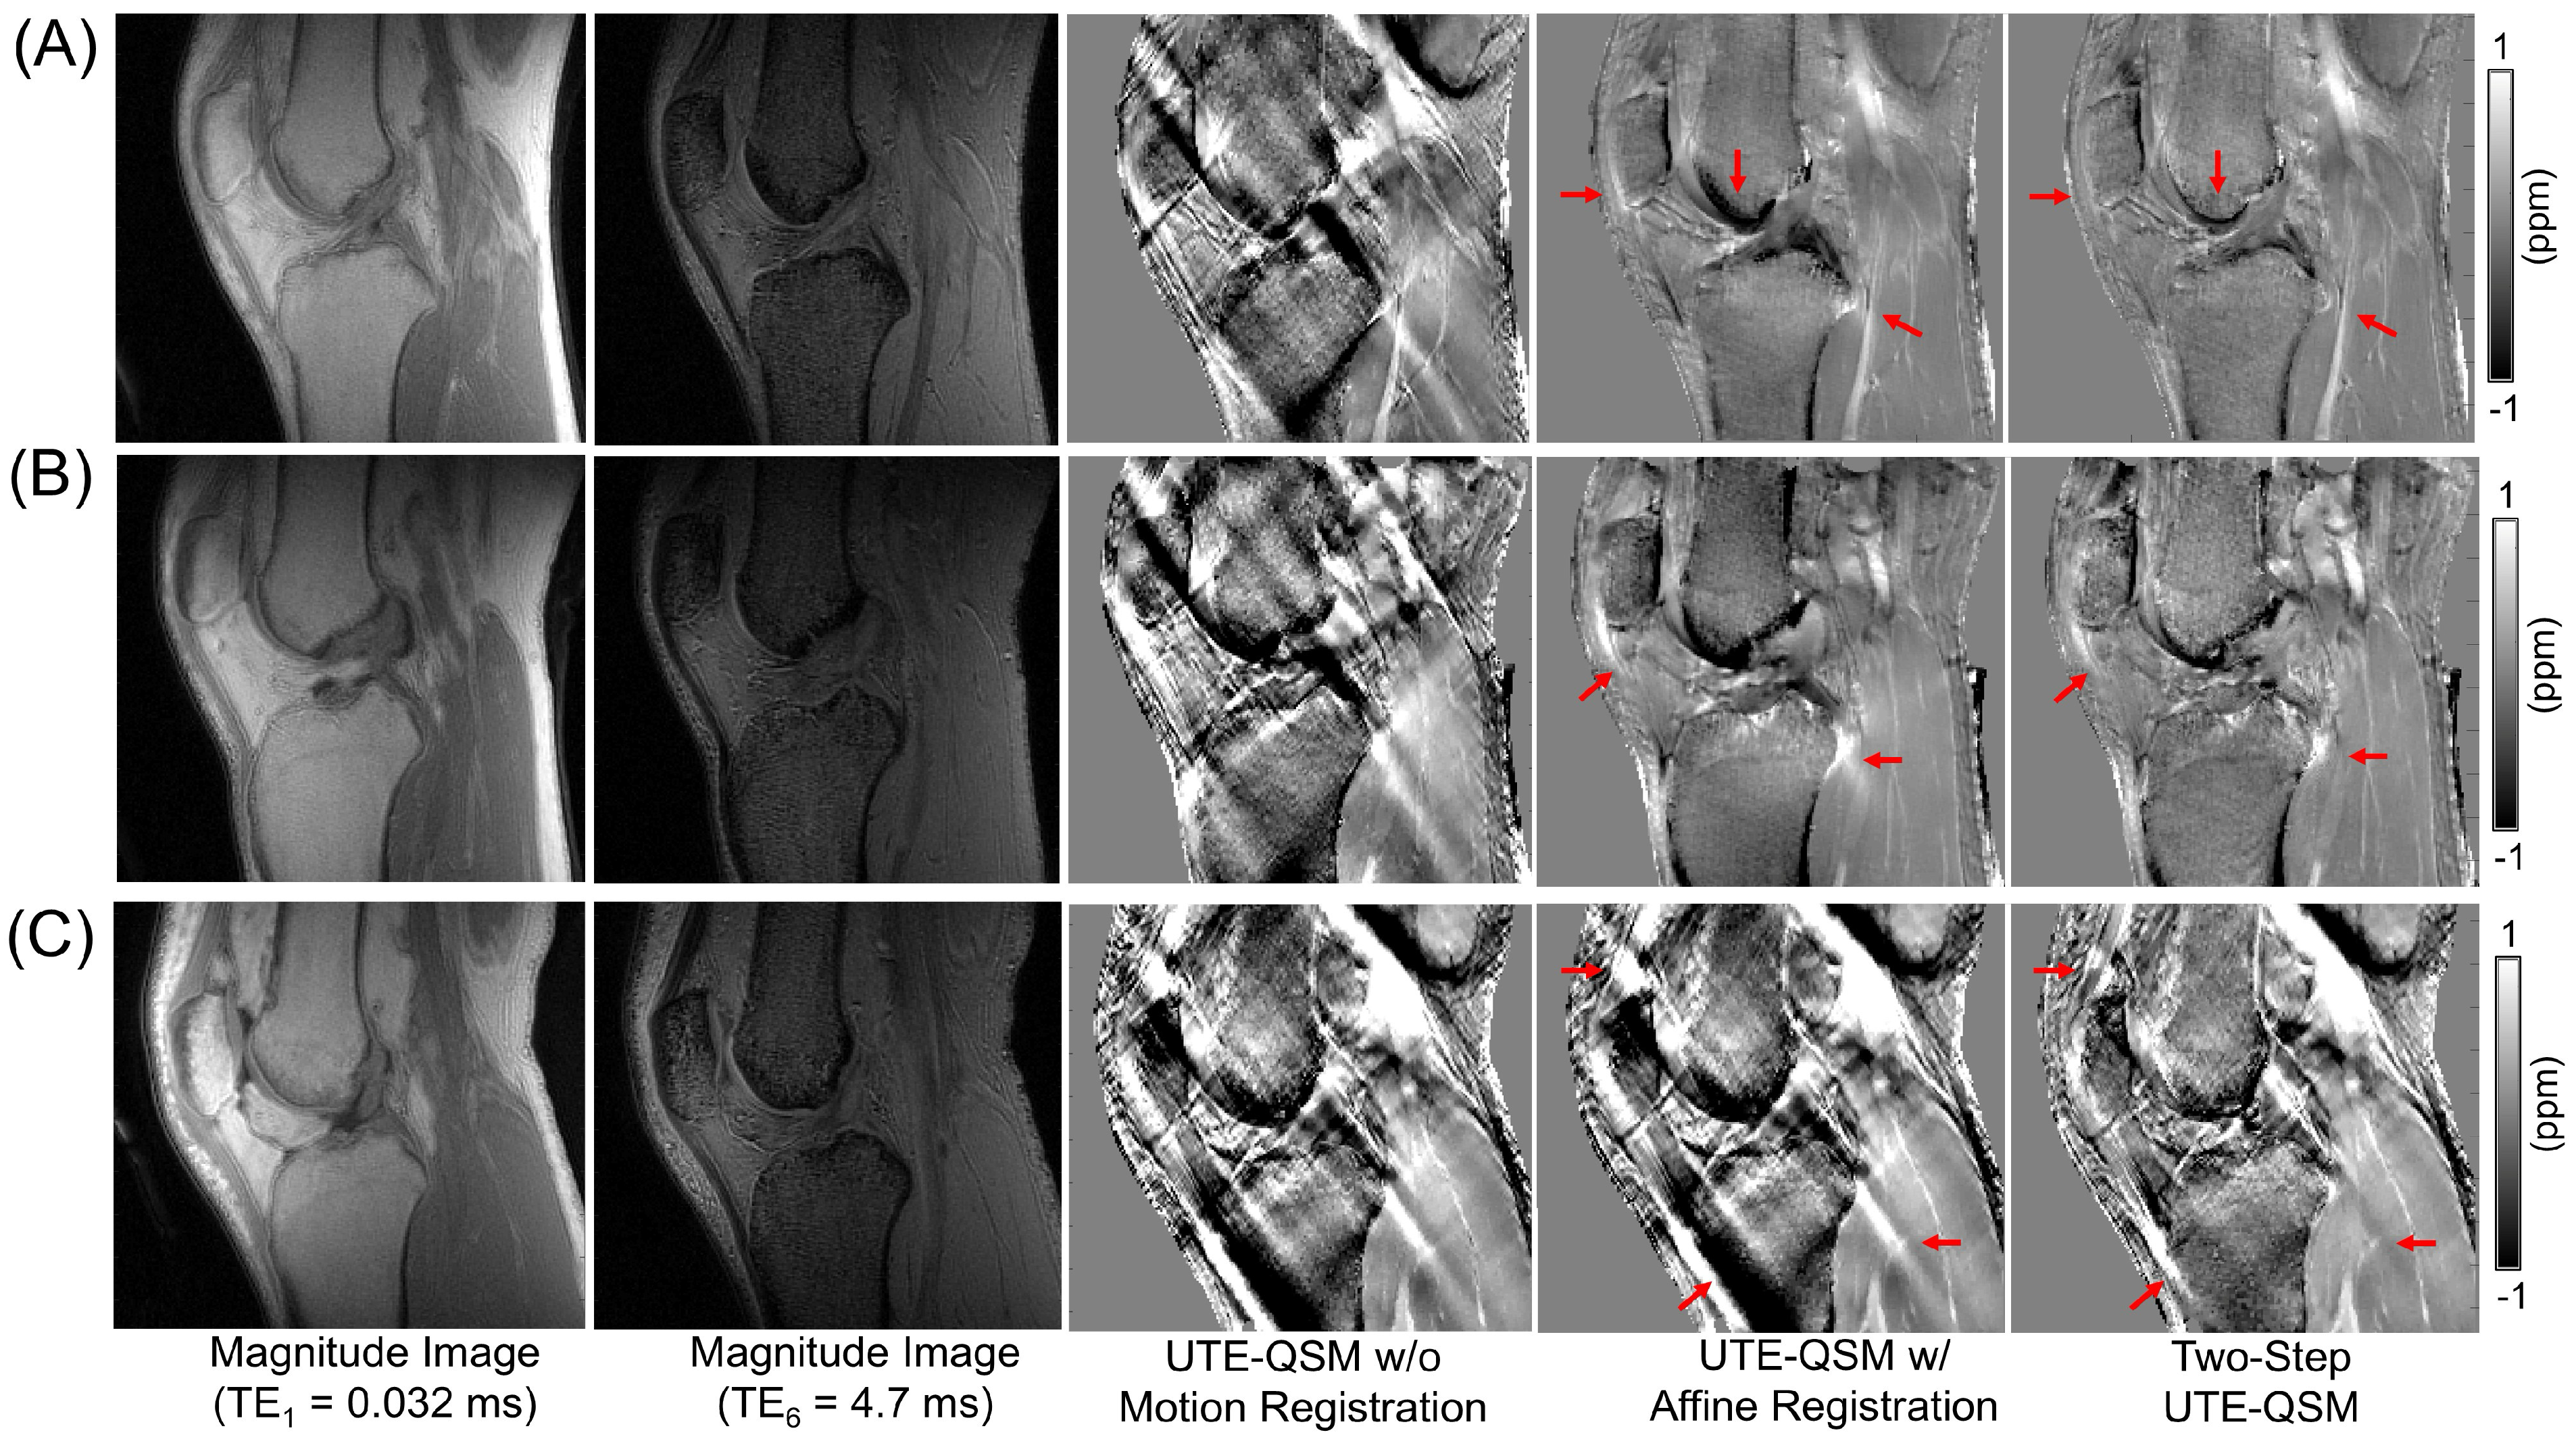

3.4. UTE-QSM on the Knee and Ankle Joints